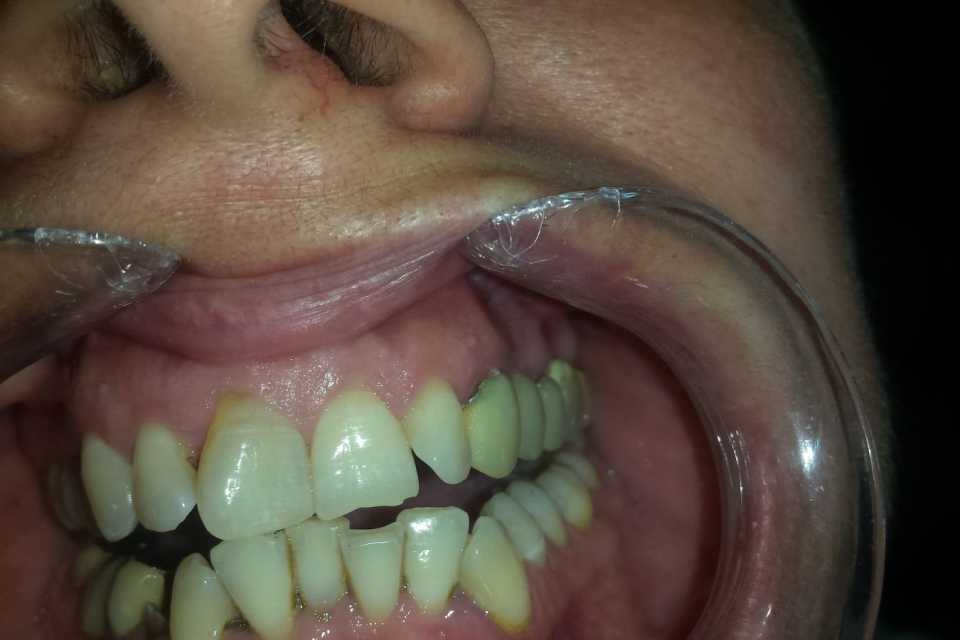

Pacienta s-a prezentat în cabinet din motive estetice și funcționale, acuzând sângerări gingivale și un miros neplacut. Am îndepărtat vechea lucrare, am refăcut tratamentele de canal, bonturile protetice și am slefuit bonturile cu prag.